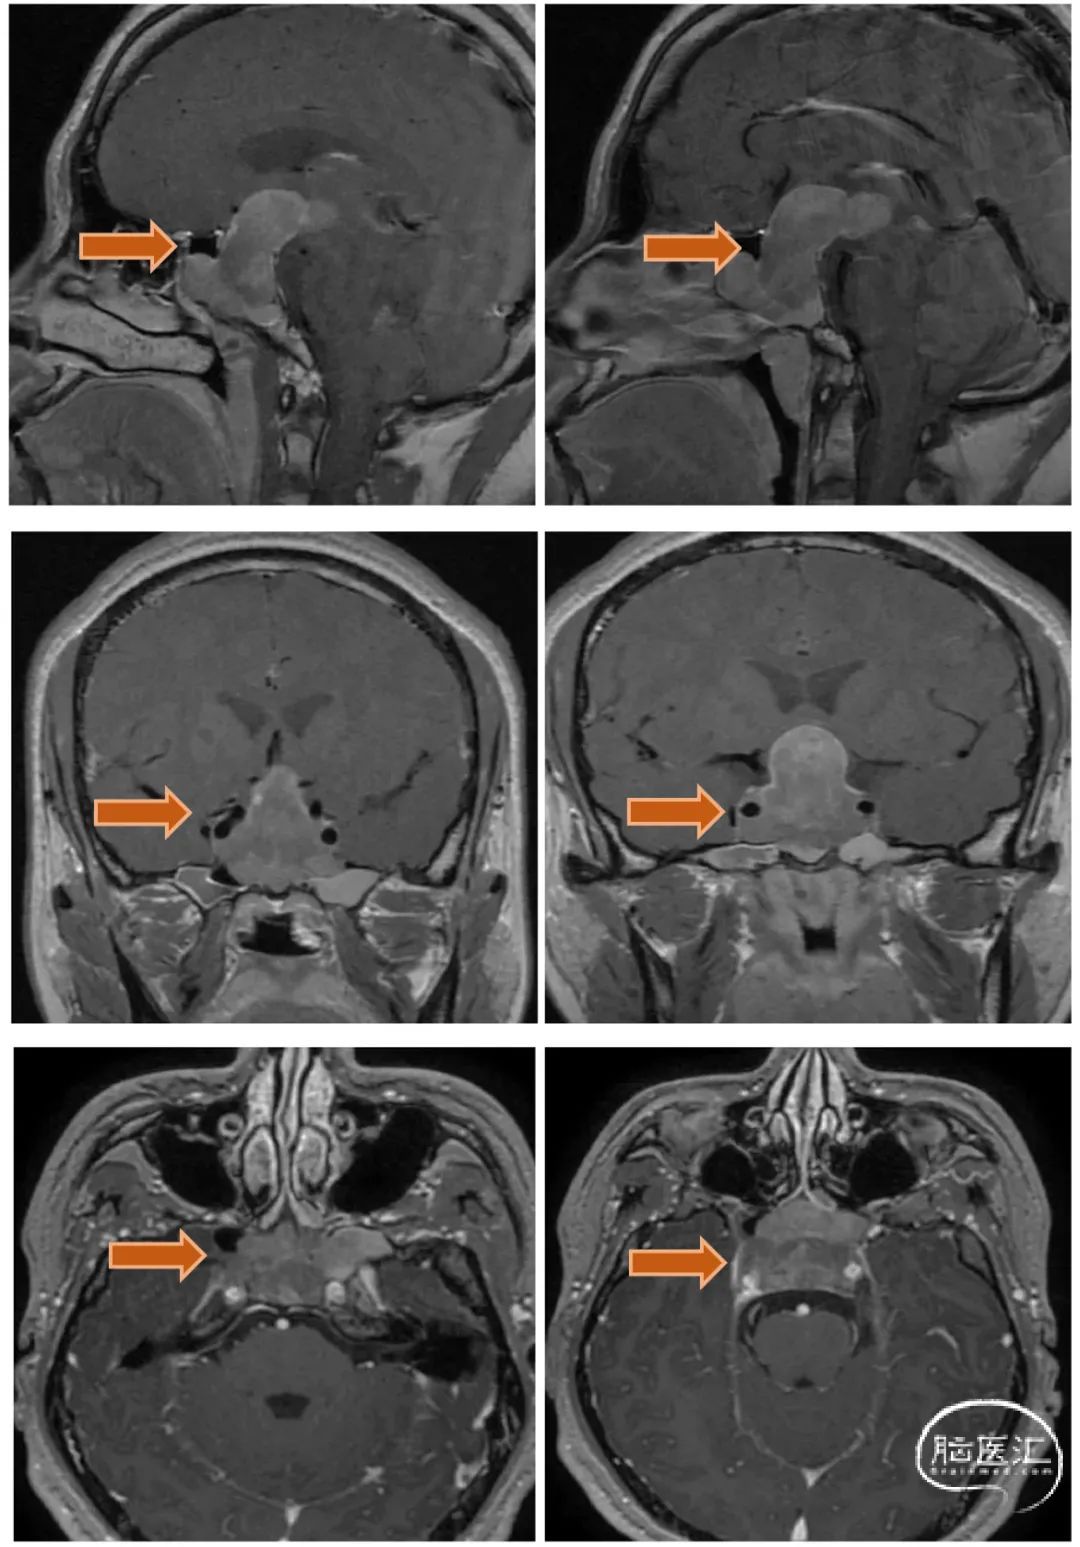

2、MRI显示该患者肿瘤巨大,向鞍上方向生长,上方突破鞍隔进入三脑室,下方突破鞍底进入蝶窦腔。因此,肿瘤有较强的侵袭性,突破硬膜,侵犯骨质,生长进入蛛网膜下腔脑室内,这部分肿瘤对手术来说难度极大。

患者第一次经鼻垂体瘤切除手术后随访8个月,肿瘤下塌进入鞍内,入院行第二次手术治疗。

下图为第二次手术术前MRI

1、经过第一次手术和随访等待,三脑室内肿瘤已逐步下塌至鞍内,与三脑室、下丘脑之间结构清晰,手术安全性已大大提高。